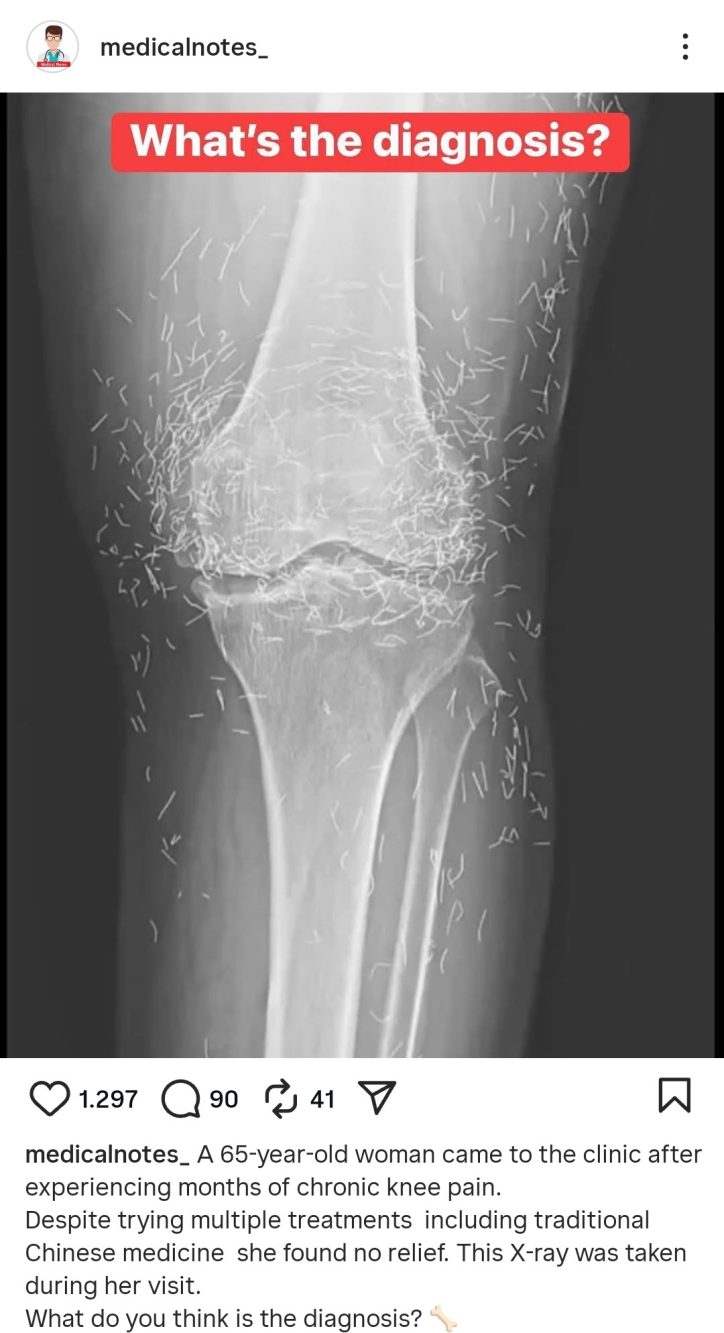

I dottori hanno eseguito radiografie e accertamenti clinici, scoprendo non solo i segni tipici dell’artrosi al ginocchio – come indurimenti ossei e accrescimento anomalo del tessuto – ma anche una moltitudine di fili d’oro innestati nei tessuti molli. L’episodio è stato documentato sulle pagine del New England Journal of Medicine, una delle riviste scientifiche più autorevoli al mondo.

La cosiddetta “gold thread acupuncture” consiste nell’inserimento di sottilissimi fili d’oro sterile attorno alle articolazioni. Secondo chi la pratica, questi frammenti metallici dovrebbero stimolare costantemente i tessuti, migliorando il flusso energetico e riducendo il dolore cronico. Tuttavia, la medicina accademica sottolinea che non esistono evidenze scientifiche a supporto di tali benefici.

Anzi, i rischi risultano documentati: i frammenti possono spostarsi nei tessuti, provocare cisti o infiammazioni, oltre a rendere impossibili esami fondamentali come la risonanza magnetica. I medici sudcoreani hanno spiegato che il caso della donna non rappresenta un episodio isolato, ma un esempio di come la fiducia in pratiche alternative possa talvolta peggiorare la situazione clinica di un paziente.